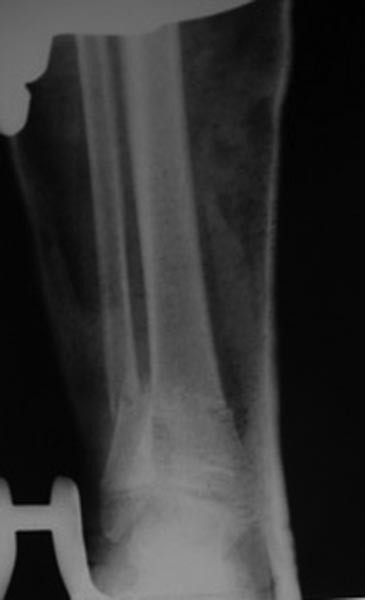

Переломы оскольчатые обеих бёдер в н/3, открытые. Раны ушиты в отличном

состоянии.

На одном бедре межмыщелковый перелом и там мыщелки немного разъехались.

Голень там тоже сломана в н/3 обе кости. Снимок голени в боковой

проекции сделан не был.